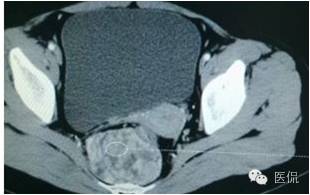

CT平扫(CT值23HU)

增强动脉期(CT值31HU)